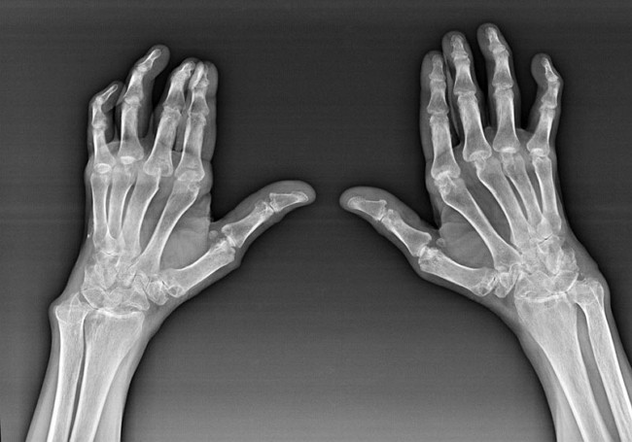

Romatoid artrit, insan bağışıklık sisteminin vücudun kendi dokularına zarar verdiği bir hastalıktır. Başka bir deyişle, romatoid artrit otoimmün bir patolojidir. Bu hastalık da sistemiktir, çünkü birçok doku bundan etkilenir (Kaslar, eklemler, gemiler, vb.) ve organlar (Kalp, böbrekler, akciğerler, vb.) vücutta.

Romatoid artritin altında sistemik bir hastalık olmasına rağmen, daha büyük ölçüde eklemler acı çekerken, diğer dokuların ve organların lezyonu arka planda. Bu hastalık ile hemen hemen her tür fırça eklemi etkilenebilir (Kollar, karpal yollar, metakarpal-falanks, phalanks eklemleri). Lezyon genellikle simetriktir (onlar. Aynı eklemler etkilenir) Her iki elinde, şişlik, hasarlı eklemlerde ağrı eşliğinde. Sabahları, yataktan kalkma sırasında, etkilenen eklemlerde yaklaşık 1 saat sürebilen ve daha sonra bir iz bırakmadan kaybolabilen biraz sertlik vardır.

Sıklıkla fırçanın etkilenen eklemlerinin yakınında romatizmal artrit ile (daha sık piyano-falanks, phalanks eklemleri) Romatoid nodüller görünür. Cildin altında bulunan yuvarlak bir formasyondur. Fırçada, bu oluşumlar çoğunlukla arkada ortaya çıkar. Palpasyonda, yoğun, aktif olmayan, ağrısızdırlar. Bunların sayısı değişebilir.